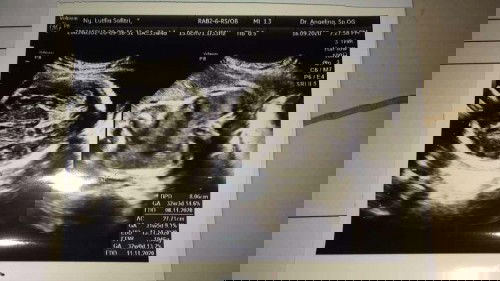

Bb janin yg mana

Bun mau tanyaa dongg ini bb janin nya ada gak yg mana ya brp bb nya aku gak paham bun, bunda bunda yg paham tolong respon nya yaaa🥺🥺